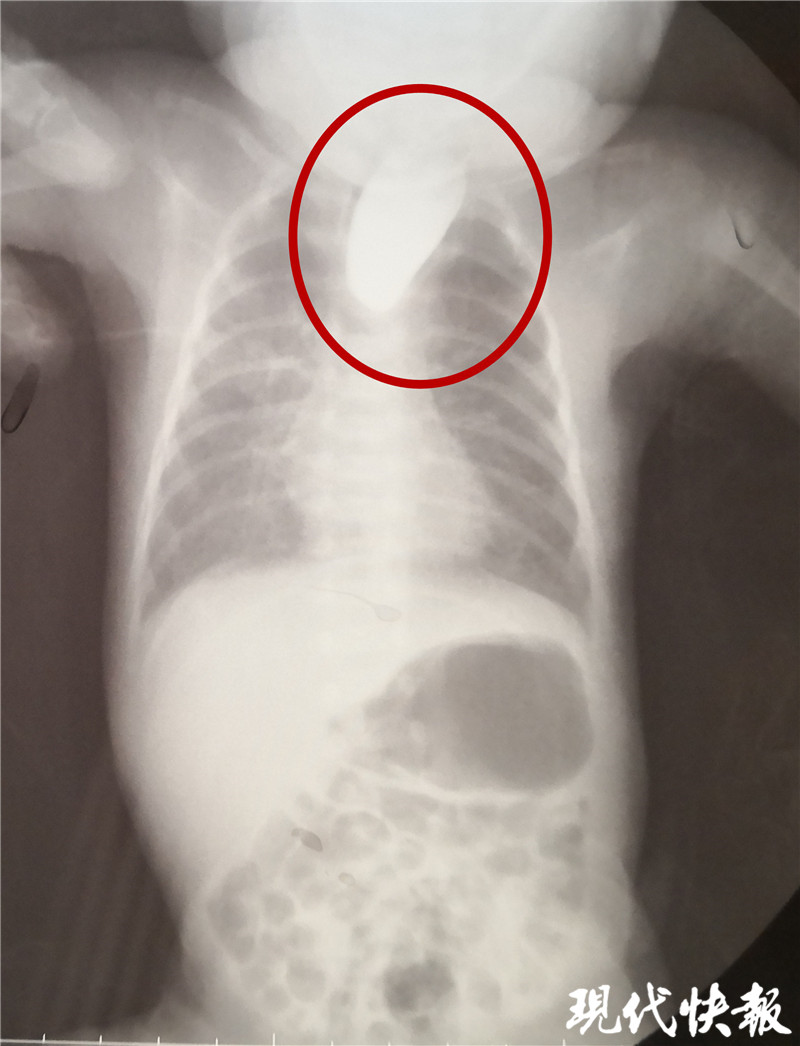

△食道閉鎖

現(xiàn)代快報記者了解到,9月8日,東東從當(dāng)?shù)蒯t(yī)院轉(zhuǎn)入淮安市婦幼保健院治療,檢查顯示東東的食道是個“死胡同”,明確診斷為食道閉鎖。“從片子上看,這個白色的造影劑到了食管上端就無法向下流了,說明孩子的食管上端是不通的、閉塞的。同時,孩子腸腔里面有氣體,這個氣體是通過氣道到食管的遠(yuǎn)端,到達(dá)胃和腸道內(nèi)。”淮安市婦幼保健院小兒外科副主任醫(yī)師夏順林說,這個寶寶如果不及時手術(shù),就會面臨兩個問題,一個就是唾液咽不下去,會嗆入肺部形成吸入性肺炎,同時胃和食管遠(yuǎn)端與氣管相通,胃內(nèi)的胃酸容易反流到氣道里面,進(jìn)入肺部形成化學(xué)性肺炎。